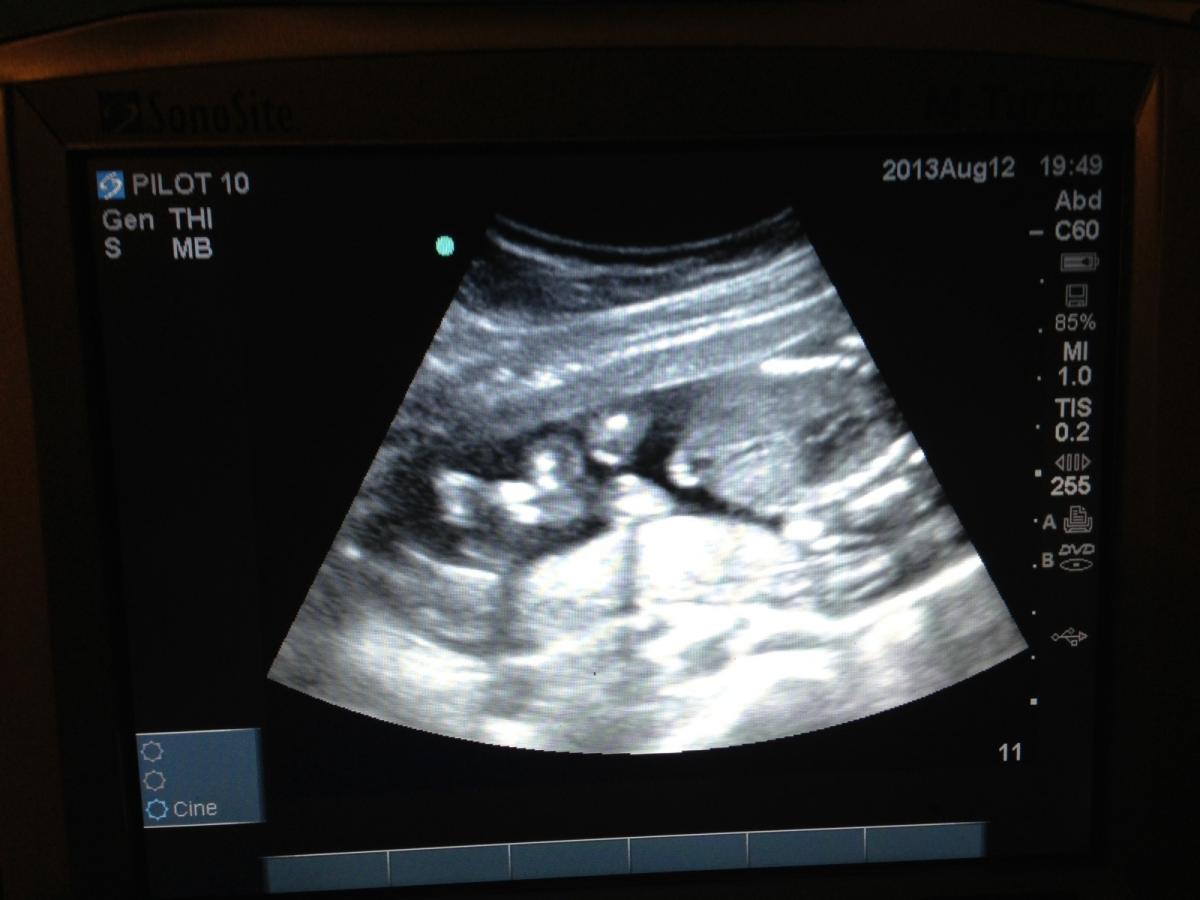

Anonym bruker Skrevet 15. august 2013 #1 Skrevet 15. august 2013 Gutt eller jente? Hva tror dere? Anonymous poster hash: 07095...36f

Anonym bruker Skrevet 15. august 2013 #7 Skrevet 15. august 2013 Skal vistnok være et tverrsnitt. Midt i bilde mot høyre er bekkenet og kjønnet. Jmor mente jente, men jeg er like forvirret som dere! Anonymous poster hash: 07095...36f

Anonym bruker Skrevet 15. august 2013 #8 Skrevet 15. august 2013 For meg ser det ut som jente I alle fall veldig likt ultralydbilde jeg har av mine 3 jenter Mener det på grunn av de 3 lyse strekene litt til høyre på midten Anonymous poster hash: 4f913...e7d

Anonym bruker Skrevet 15. august 2013 #9 Skrevet 15. august 2013 Vi fikk sett et bilde som var litt annerledes enn deres, men der det var tre parallelle hvite streker, og det skulle være kjønnsleppene. Så på deres bilde er det jo også tre hvite parallelle streker til venstre på den store delen til høyre. (Var det forståelig?) Så kan være det jordmor mente viser at det er jente? Anonymous poster hash: 8c7e4...f37

Anonym bruker Skrevet 15. august 2013 #11 Skrevet 15. august 2013 Ah, da er det jente! Gratulerer så mye (du hadde fått et gratulerer ved gutt også altså)De tre strekene du ser, det er det kun jenter som har Hvis jeg forstod riktig hvor du mente kjønnet var da, selvfølgelig Anonymous poster hash: 93013...1d2

Anonym bruker Skrevet 15. august 2013 #12 Skrevet 15. august 2013 Gutt eller jente? Hva tror dere? Anonymous poster hash: 07095...36f Garantert jente! Jeg har ultralydbilder av mine to jenter som er nesten identiske. Anonymous poster hash: 716ec...514